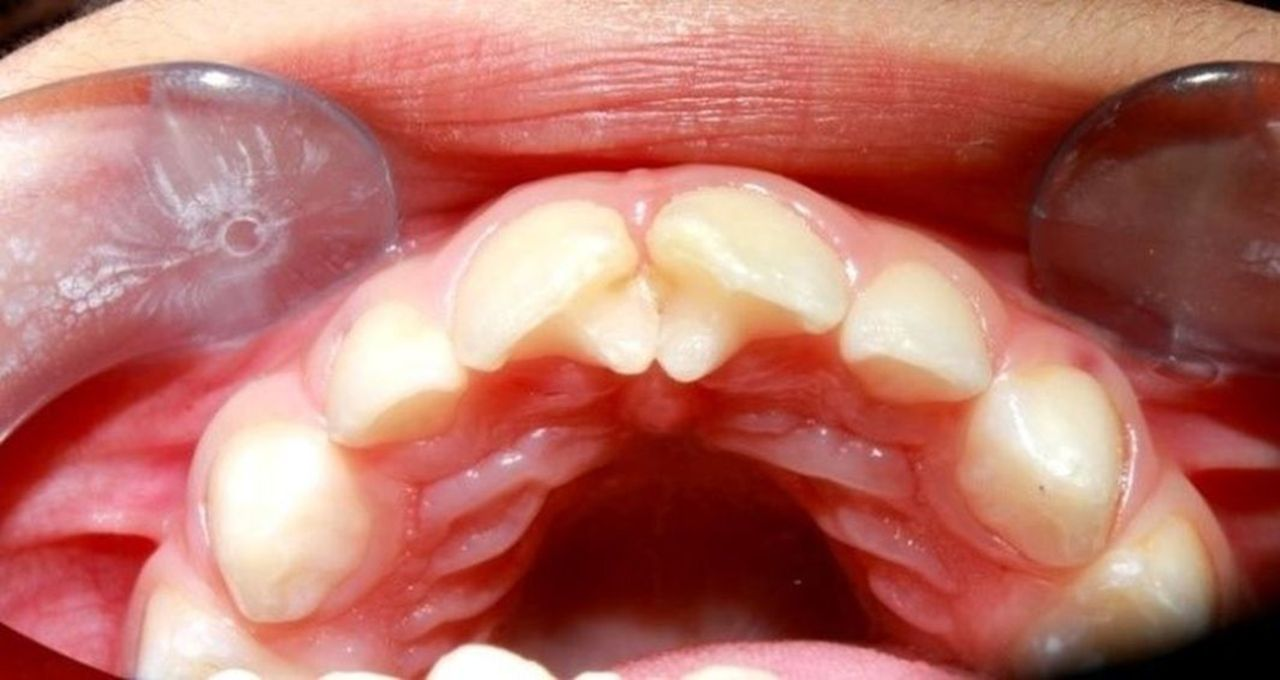

a) Germination – single enamel organ – 2 teeth develop

- 2 crowns share same root canal

- Aet: Trauma

b) Fusion – 2 tooth germs fuse by dentine ± pulp – forms single large tooth structure